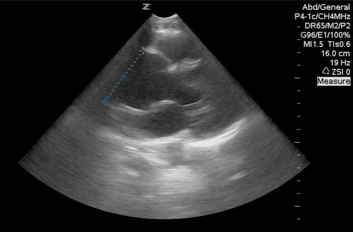

QA of the Day: PSL view and can just make out a massively dilated aortic root! #pocus #foamed #foamus